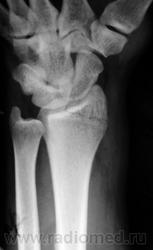

Пол пациента: Женский пол Тип патологии: Травма Область исследования: Скелетно-мышечная система Методы исследования: Rg Травма. Направлен на рентгенографию лучезапястного сустава https://radiomed.ru/sites/default/files/styles/case_slider_image/public/user/12/12.201307290023.jpg?itok=H4YeS5lg https://radiomed.ru/sites/default/files/styles/case_slider_image/public/user/12/13.201201010021.jpg?itok=RG4hVF1Z https://radiomed.ru/sites/default/files/styles/case_slider_image/public/user/12/14.201307290024.jpg?itok=6cA-21Nw ID:30173 Пнд, 29/07/2013 - 17:55 #1 brainmodel Не на сайте Был на сайте: 2 месяцев 3 недели назад Зарегистрирован: 18.03.2010 - 22:04 Публикации: 2881 Внутрисуситавной перелом наружного сектора дистального эпифиза луча без смещения. Verum plus uno esse non potest. Пнд, 29/07/2013 - 21:39 #2 maker4ik Не на сайте Был на сайте: 8 лет 7 месяцев назад Зарегистрирован: 19.10.2011 - 17:49 Публикации: 2682 Должно хорошо срастись.

Внутрисуситавной перелом наружного сектора дистального эпифиза луча без смещения.

Должно хорошо срастись.